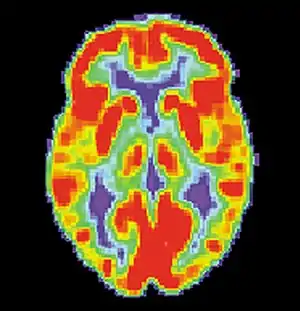

The pursuit rotor task is a simple pure visual-motor tracking test that has consistent results within age groups.[20] This displays a measurement of procedural memory as well as demonstrates the participant's fine motor skills. The pursuit rotor task tests the fine-motor skills which are controlled by the motor cortex illustrated by the green section below.